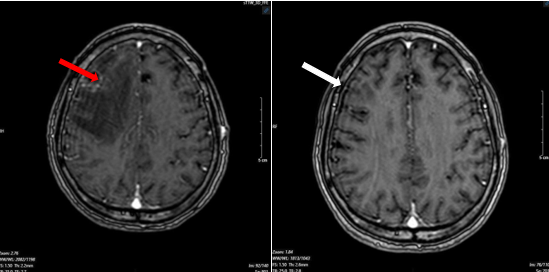

Bệnh nhân được chụp cộng hưởng từ sọ não, phát hiện khối u vùng trán phải, kích thước 17 x 20 mm gây phù não rộng xung quanh theo dõi tổn thương thứ phát

Hình 1. Hình ảnh cộng hưởng từ sọ não ngày 25 tháng 03 năm 2025 (hình bên trái: xung T1; hình bên phải: xung T2) cho thấy khối u não vùng trán phải (mũi tên).

Sau 3 chu kỳ điều trị, bệnh nhân được làm lại các xét nghiệm và chụp lại kiểm tra. Kết quả cho thấy kích thước các khối u đều giảm đáng kể, thẻ hiện sự đáp ứng tốt với liệu trình điều trị của bệnh nhân

Hình 6. Hình ảnh phim chụp cộng hưởng từ não ngày 12 tháng 07 năm 2025 (mũi tên trắng) so với ngày 25 tháng 03 năm 2025 (mũi tên đỏ) cũng thể hiện kích thước khối u đã giảm đáng kể so với phim chụp cũ.